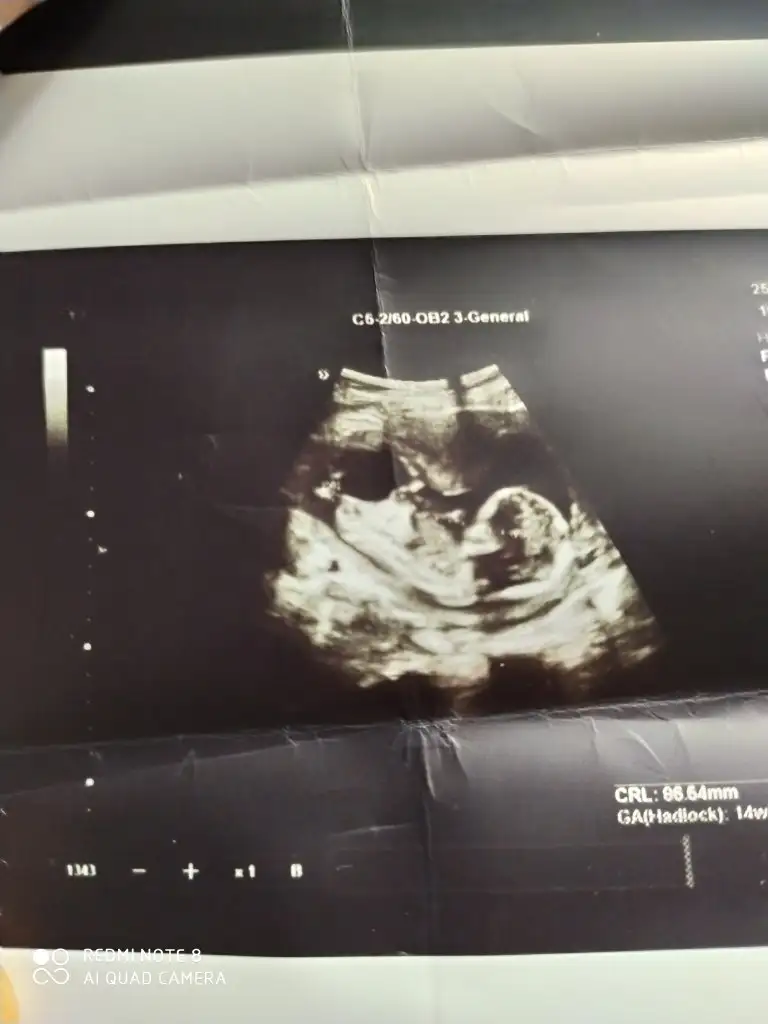

bu benim kızım ın kesesi altı haftalık sizlerin cinsiyeti ne oldu çok merak ettim sağlıklı sıhhatli kucağa almayı nasip etsin

6 haftalik cinsiyet nedir bilenler lutfen yazsin